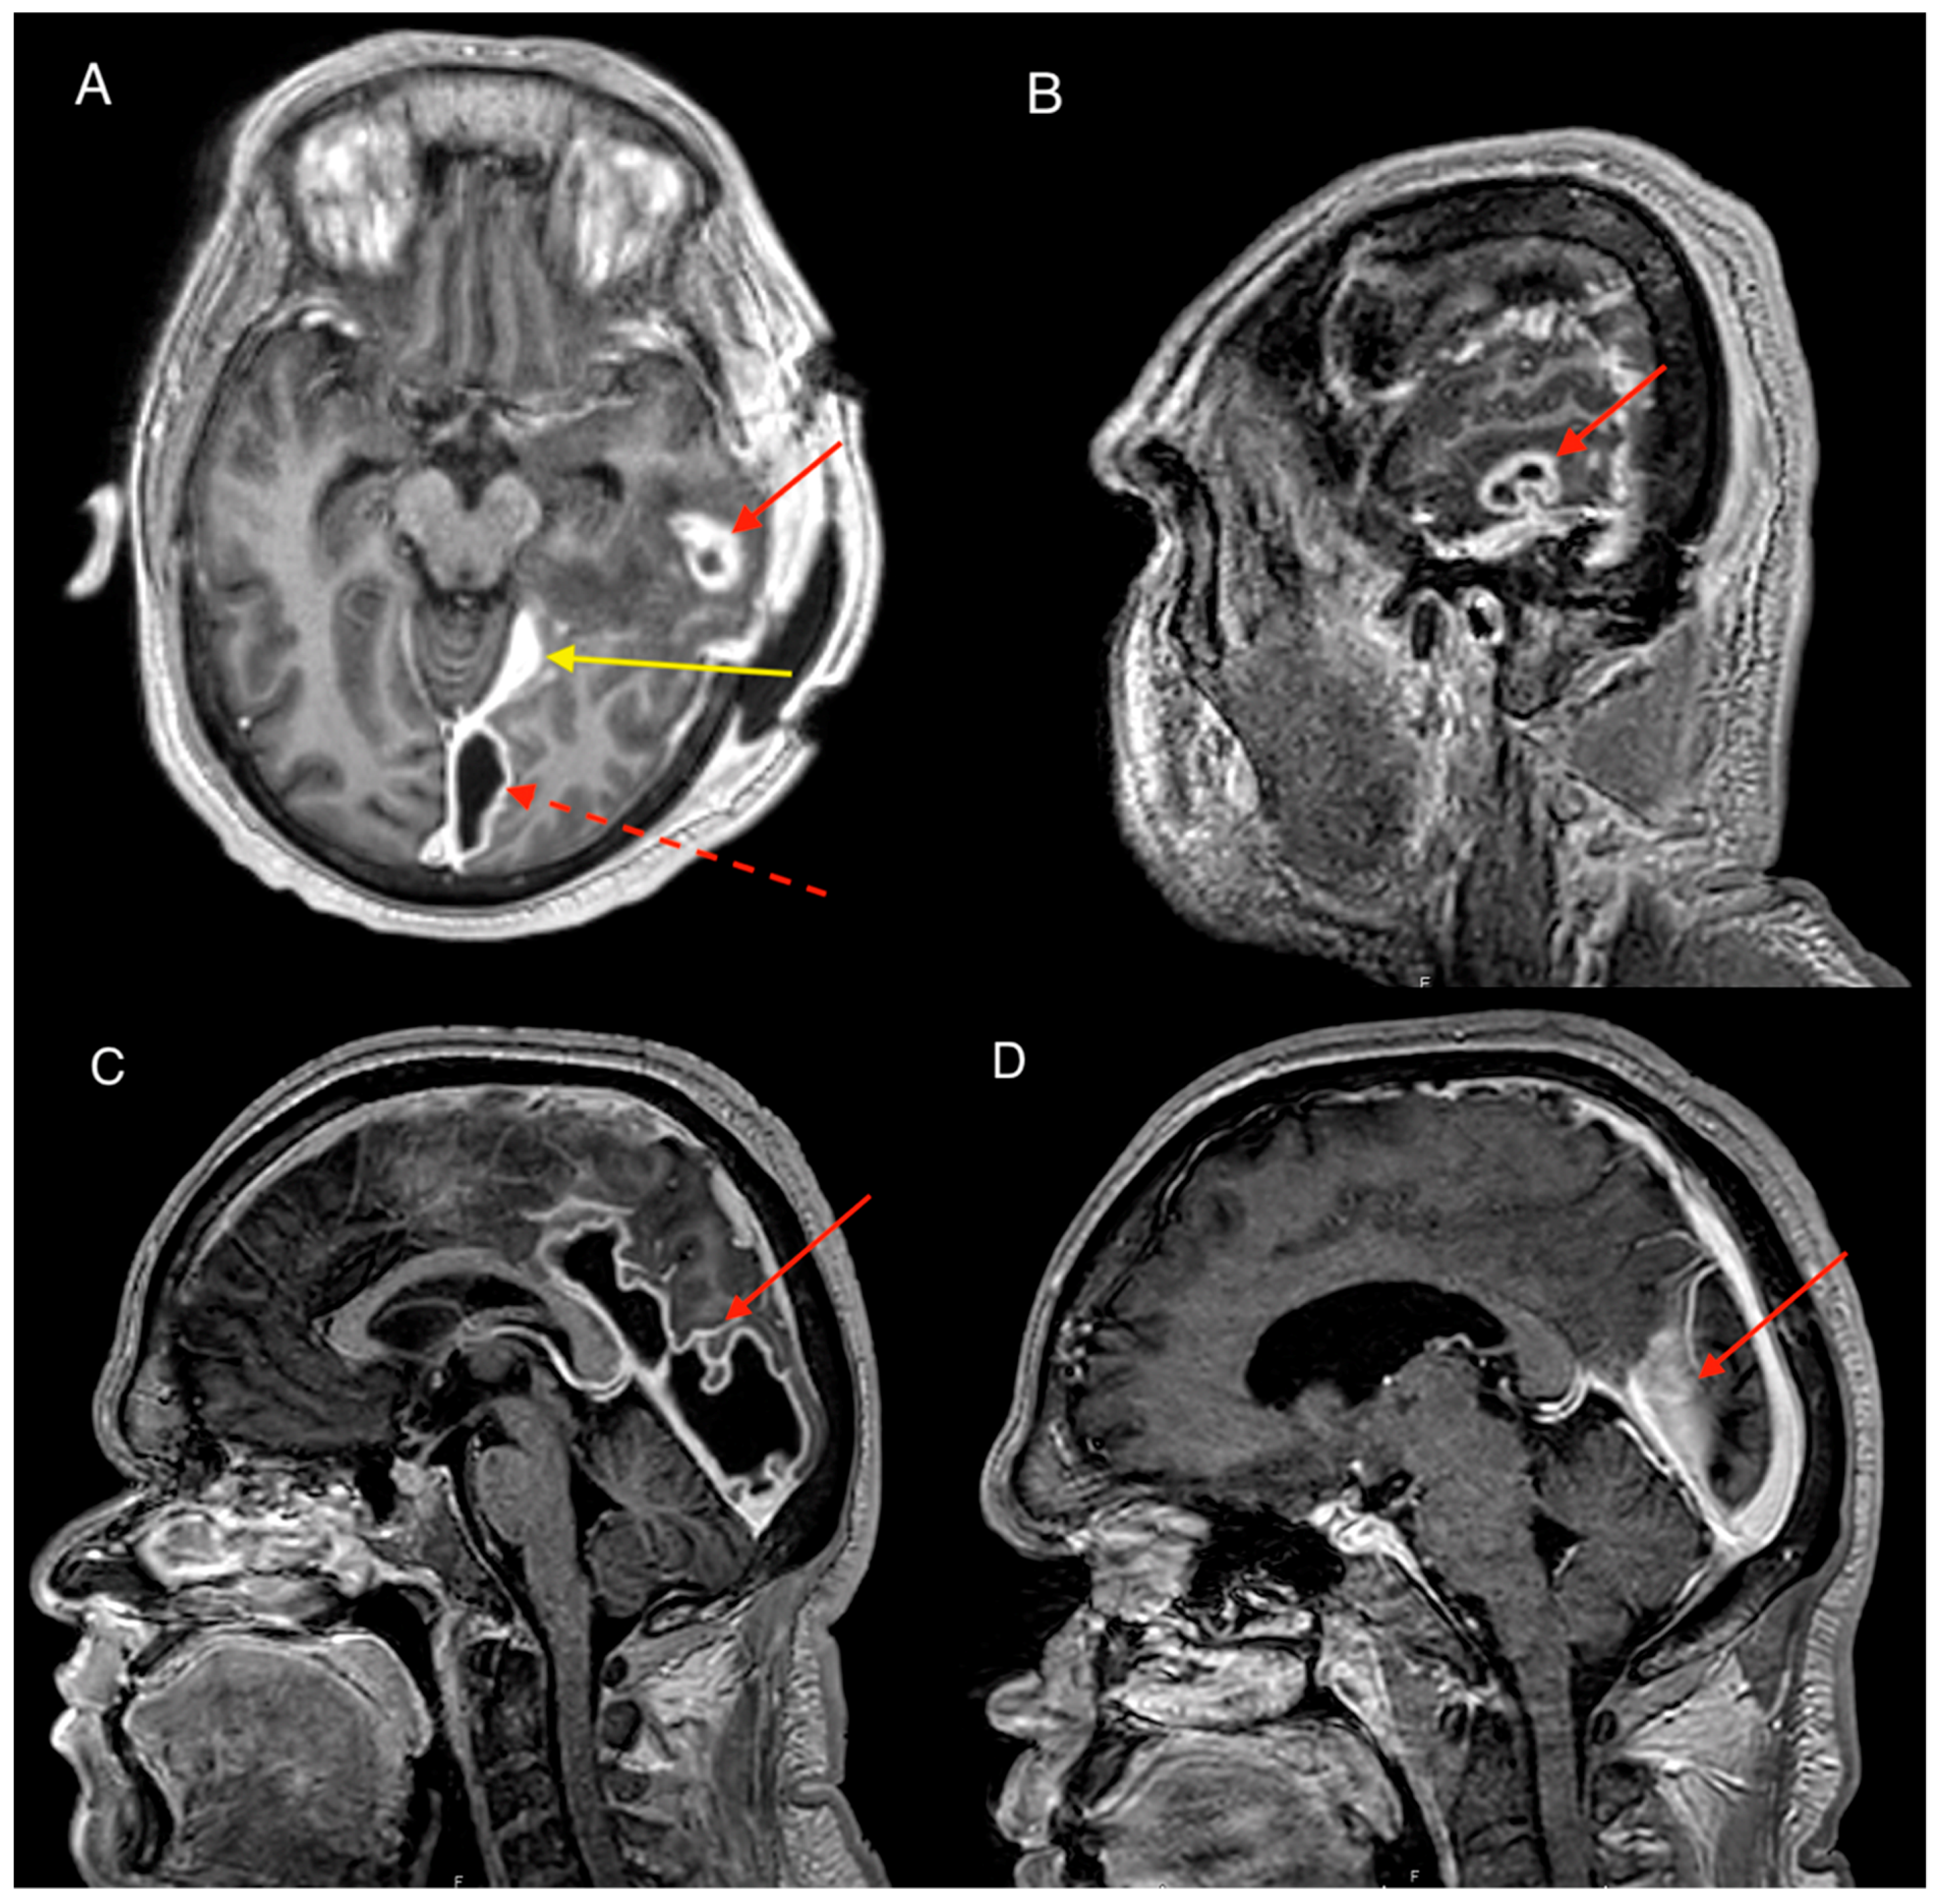

A 32-year-old Aboriginal male presented to the local community doctor 100 km from Darwin NT Australia with a 1-week history of severe headaches and vomiting. On presentation the patient had fevers of 40.2 degrees Celsius but otherwise had normal vital signs. He was expediently transferred to our service via air ambulance. Patient had a background history of cognitive impairment and stage 2 chronic kidney disease. He was a non-smoker with moderate intake of alcohol in the community. Clinical examination showed no neurological deficits with Glasgow coma scale (GCS) of 14/15 with 1 point lost in verbal test due to baseline communication disability. Blood tests revealed white cell count (WCC) of 19.9 × 109/L (neutrophilia) and c-reactive protein (CRP) count of 213 mg/L. Blood cultures were also taken which returned negative. The combination of symptoms and suspicion of an intracranial infection prompted a computerized topography (CT) brain scan which revealed an extra-axial collection with rim enhancement. The collection was located at the floor of the left middle cranial fossa with associated vasogenic edema of the surrounding brain suggestive of a subdural empyema (Figure 1A,B). Closer inspection on CT of the ear canal revealed opacification of the middle ear, mesotympanum and epitympanum with consistent findings on the magnetic resonance imaging (MRI) (Figure 1C,D). During the MRI the patient experienced seizures and was loaded with levetiracetam and placed on regular doses.

Figure 1. Imaging on presentation, contrast computerized topography (CT) and magnetic resonance imaging (MRI) brain T1 contrast axial and sagittal views. (A) Axial CT scan with contrast showing subdural collection in the left middle cranial fossa (red arrow). (B & D) Sagittal CT with contrast and MRI T1 with contrast showing collection above the tentorium. Note minimal contrast enhancement of the collection with no clear evidence of cerebral oedema representing early stages of intracranial subdural empyema (ISE). (C) Axial MRI T1 with contrast. Note area of contrast enhancement at the floor of middle cranial fossa on the petrous part of temporal bone (dotted arrow) correlated with the dural defect found intraoperatively.